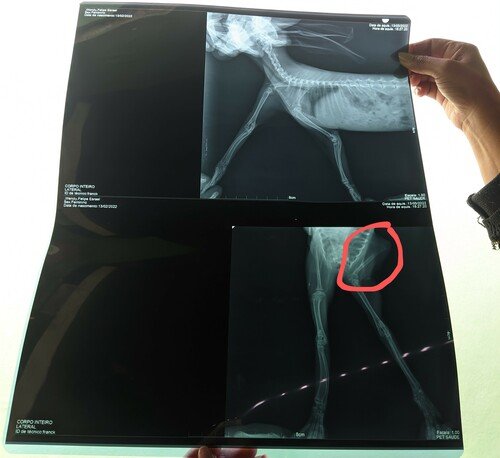

Olá, meu nome é Wendy, sou uma coelhinha mini lop muito esperta, tenho apenas 3 meses de vida, gosto muito de correr e pular. Mas, acabei fraturando meu bracinho direito, e para recolocar no lugar, necessito fazer uma cirurgia, que custa $1.500,00, e o meu dono, Felipe, não consegue arcar com todos os custos (cirurgia, consultas, remédios, raio-x), por isso, venho aqui pedir a sua ajuda para que eu consiga fazer a minha cirurgia, e assim, consiga voltar a pular e correr como eu amo fazer. Você pode me ajudar?